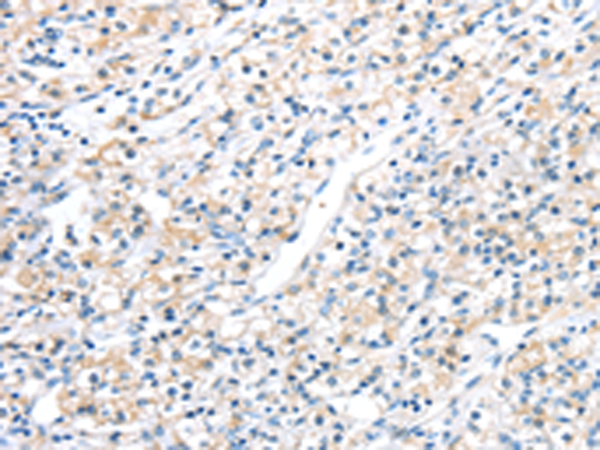

分类: 科研抗体货号: P11855别名: IMPD; RP10; IMPD1; LCA11; sWSS2608应用: WB,IHC反应种属: Human, Mouse, Rat